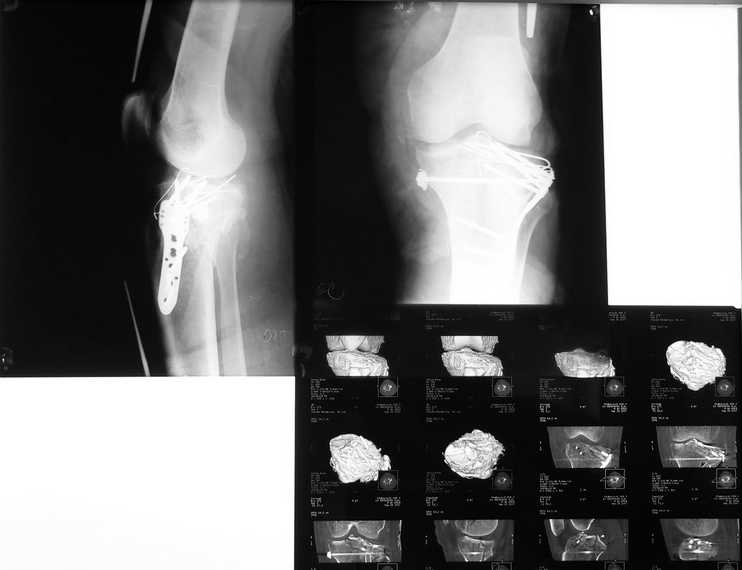

Результат после операции

R-гр контроль и КТ после синтеза межмыщелкового перелома голени.

Первичные снимки в сообщении от 20 сентября. Критика коментарии

приветствуются. С уважением Пак Л.